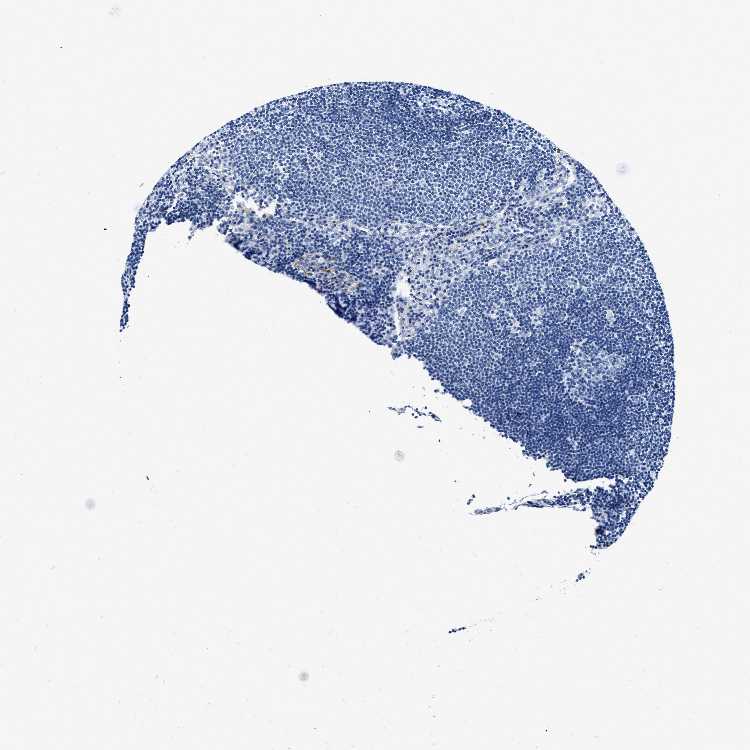

LYMPH NODE - HPA RNA-seqi

The RNA-seq details section shows detailed information about the individual samples used for the transcript profiling and results of the RNA-seq analysis.

Information about each individual sample is listed below, including gender, age, a tissue section image and estimated fractions of cell types. nTPM (normalized transcripts per million) values give a quantification of the gene abundance which is comparable between different genes and samples.

Average nTPMi

Max subtype nTPM is the value for the subtype with the largest average nTPM across the subtype samples.

21.5

overview

Male, age 34

Lymph node sample 173

nTPM: 17.3

Cell types%

Lymphocytes:

85

Other cell types:

15